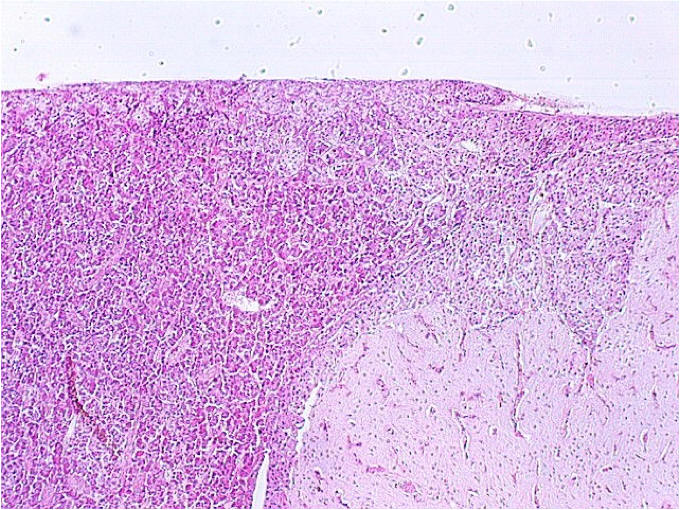

Look at your slide of the human pituitary with your naked eye. You should see a cellular region and a more fibrous region.  Then view each region with your microscope under low power.  The above photograph shows a cat pituitary.   The cellular region to the left is the pars distalis.  The fibrous region to the right is the pars nervosa.  In the cat, there is a more distinct "pars intermedia", which is seen at the upper left edge of the pars nervosa.  What is the embryologic origin of the pars distalis?________________________________   What is the embryologic origin of the pars intermedia?______________________________ What is the embryologic origin of the pars nervosa?_________________________________  Would you expect to see a distinct pars intermedia in your slide of the human pituitary?

Below is a section showing the three regions through the hypophysis